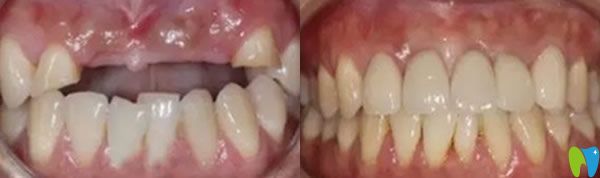

三個(gè)月后,我們又來(lái)到成都瑞爾口腔,醫(yī)生說(shuō)恢復(fù)的很不錯(cuò),牙槽骨和種植體已經(jīng)緊密結(jié)合,可以安裝基臺(tái),戴上牙冠后,牙齒咀嚼功能恢復(fù)了,可承受正常的咀嚼力量,美觀上幾乎和自然牙一樣。郝亦工醫(yī)生建議后期一定要保持好口腔衛(wèi)生健康,細(xì)心呵護(hù),這樣能夠保證種植牙的使用壽命。

在成都瑞爾口腔種植牙技術(shù)解決了老公牙齦萎縮,精神面貌也好了,不再像個(gè)糟老頭,整個(gè)人也精神起來(lái)啦!